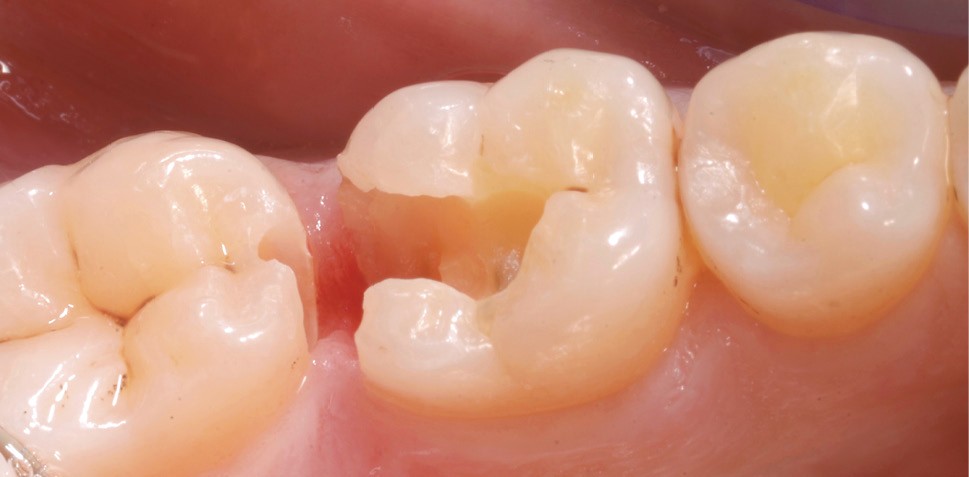

La localisation (type de dent)

Le pronostic clinique semble plus favorable pour les prémolaires que pour les molaires [3-5], car une plus grande résistance est généralement nécessaire pour les parois des molaires. Mais si 75 % des fractures à la mandibule affectent les molaires, et plus particulièrement la première molaire, au maxillaire, les fractures se répartissent équitablement entre le secteur molaire et le secteur prémolaire [6]. L’épaisseur de l’émail, la largeur de la cuspide comme les…